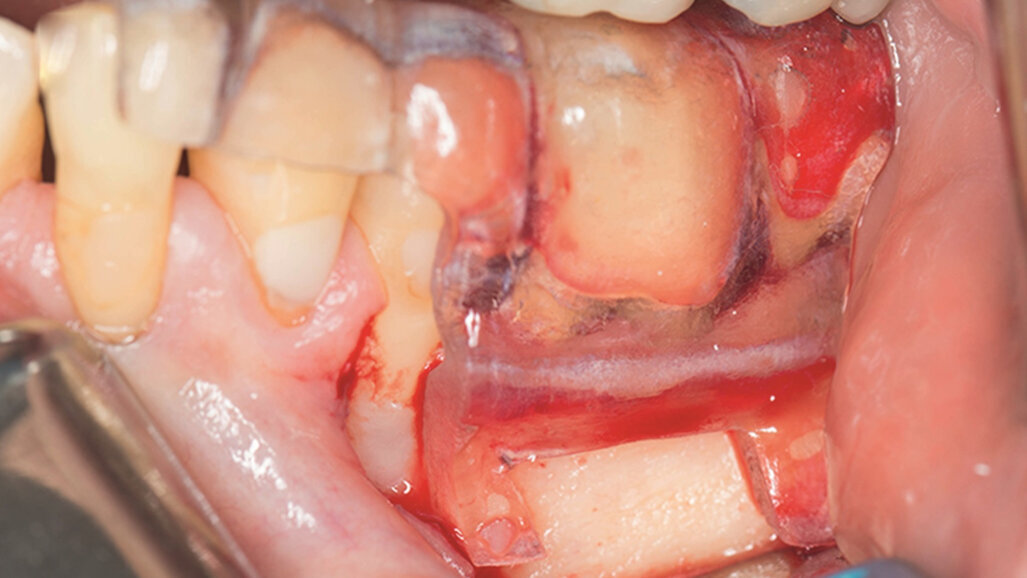

Fig. 1e–i: During microsurgery, the template was adjusted (e), …

… the limits of the cortical window were marked in the bone (f) …

… with a saw mounted in a Piezotome CUBE LED handpiece, then the bone was cut and removed (g & h) …

… to access the apical area and perform the apicectomy, apical cavity preparation and retro-filling of the mesial and distal roots (i).

Fig. 1j: Finally, the cortical window was replaced and stabilised with collagen tape.

Under local anaesthesia, a full thickness mucoperiosteal flap was reflected and the printed template was used to mark the cortical window, which was cut with a Piezotome CUBE LED handpiece (ACTEON), removed (Figs. 1e–h) and then placed in sterile saline. An apicectomy was done (Fig. 1i), and the mesial canals were retro-prepared with ultrasonic tips (NSK) and filled with EndoSequence BC RRM Fast Set Putty (Brasseler). The cortical window was then placed back and stabilized with collagen sponges in the gaps (collagen tape, Zimmer Biomet; Figs. 1j & k), and the ‑ap was sutured using 6/0 prolene suture material (Corpaul).